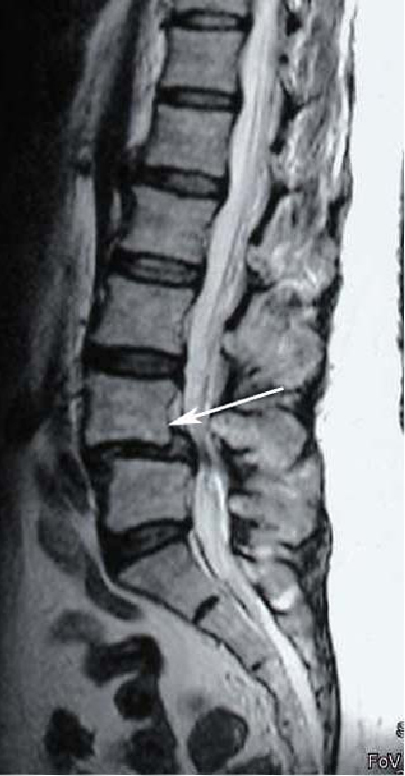

Спондилолистез

Рис. 1. МРТ поясничного отдела позвоночника. Антеролистез L4 позвонка. Стрелкой указано смещение L4 позвонка кпереди. Рис. 1. МРТ поясничного отдела позвоночника. Антеролистез L4 позвонка. Стрелкой указано смещение L4 позвонка кпереди.